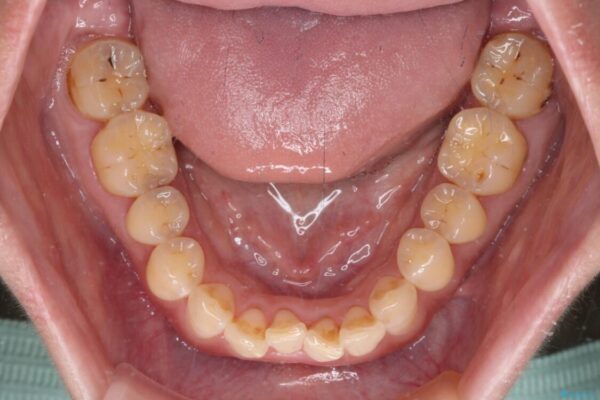

治療前

• 【モニター】飛び出た前歯を整えたい ワイヤー矯正治療 治療前画像